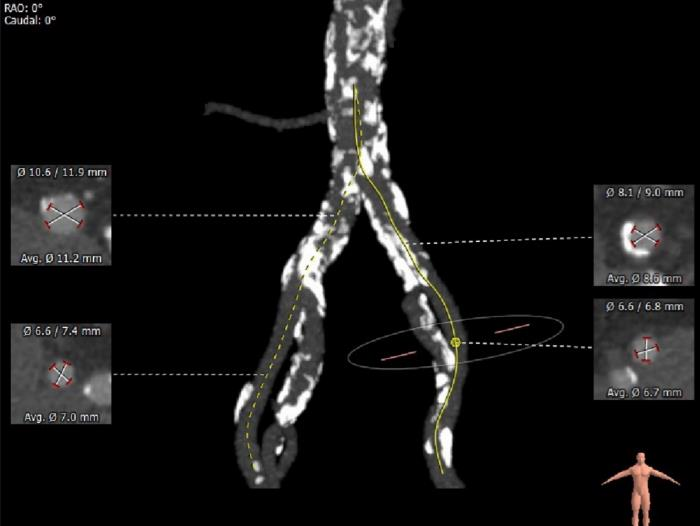

术前CT评估:

⦁ 双侧血管内径可,存在明显钙化,主动脉弓距与夹角位置可,股动脉分叉位置可,符合血管入路条件。

③患者外周血管钙化严重,入路风险较高,需注意防范外周血管风险。

外周血管及主动脉弓解剖: